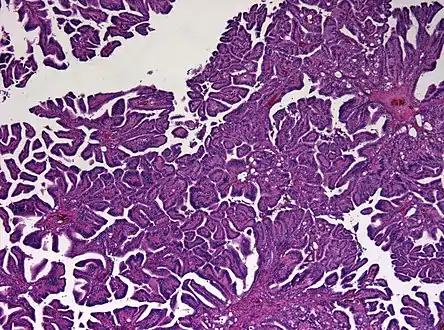

Micrograph of a choroid plexus papilloma. H&E stain.

Plexuspapillom Detail

Plexuspapillom Overview